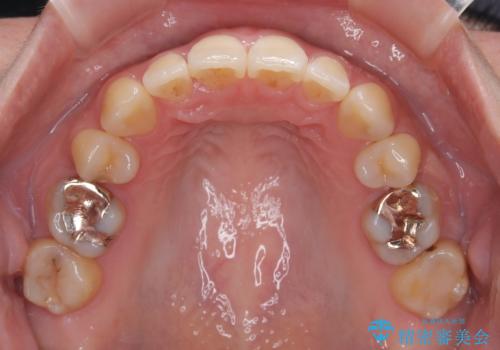

- 下顎小臼歯が欠損しており、さらに上顎が全体的に突出していることを気にして来院された患者様です。

下顎は片方の小臼歯が欠損していたため、正中がずれた上に、上下前歯が接触していない状態でした。

上顎左右の小臼歯2本および下顎小臼歯を1本抜歯し、補助装置を用いて上顎大臼歯が前方に移動しないように固定した上で、ワイヤー装置にて矯正治療を行うこととしました。